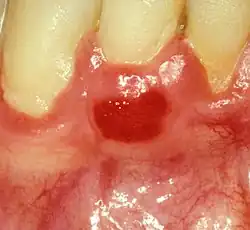

| Plasma cell gingivitis in an adult (histologically verified). |

Plasma cell gingivitis appears as mild gingival enlargement and may extend from the free marginal gingiva on to the attached gingiva.[6] Sometimes it is blended with a marginal, plaque induced gingivitis, or it does not involve the free marginal gingiva. It may also be found as a solitude red area within the attached gingiva (pictures). In some cases the healing of a plaque-induced gingivitis or a periodontitis resolves a plasma cell gingivitis situated a few mm from the earlier plaque-infected marginal gingiva. In case of one or few solitary areas of plasma cell gingivitis, no symptoms are reported from the patient. Most often solitary entities are therefore found by the dentist.[2]

The gums are red, friable, or sometimes granular, and sometimes bleed easily if traumatised.[6] The normal stippling is lost.[7] There is not usually any loss of periodontal attachment.[6] In a few cases a sore mouth can develop, and if so pain is sometimes made worse by toothpastes, or hot or spicy food.[7] The lesions can extend to involve the palate.[7]